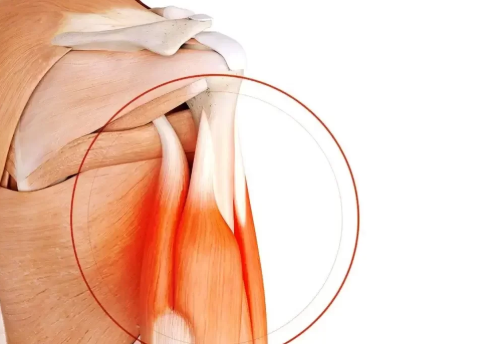

Les lésions du tendon du biceps, partielles ou totales, limitent l’amplitude de mouvement et provoquent douleur et gêne. La chirurgie de l’épaule répare la désinsertion pour retrouver une fonction normale.